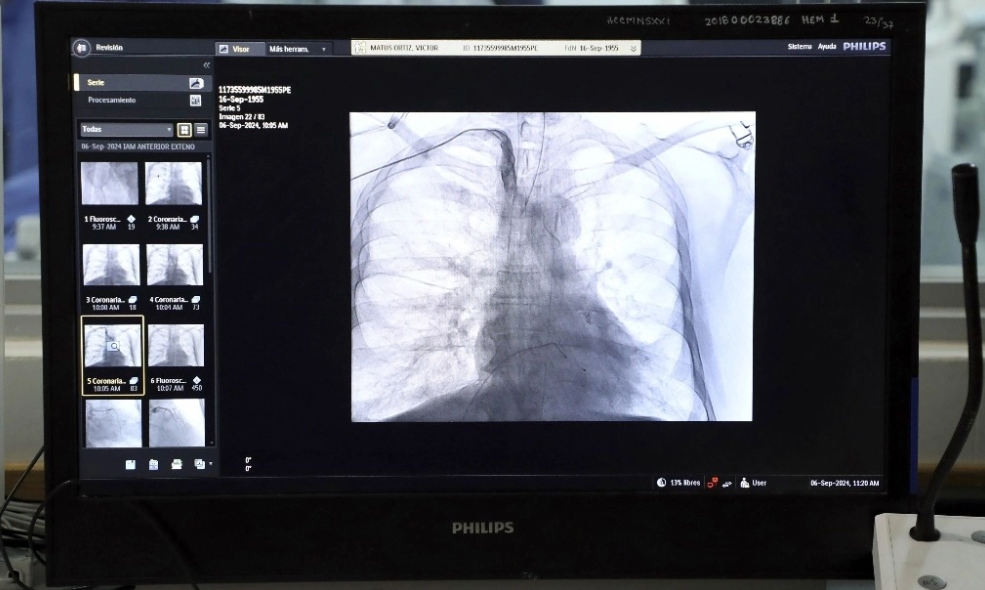

Alejandro Ricalde, cardiólogo intervencionista, explicó que el sistema de denervación renal es un dispositivo que, por medio de un catéter, se introduce a través de la arteria femoral para llegar a los nervios del sistema simpático que están cerca de los riñones. Son los encargados de generar las alertas

al organismo. Hacen que suba el ritmo cardiaco y la presión arterial ante eventos de la vida cotidiana, incluida la angustia y el estrés.

Cuando esto ocurre, apuntó Dorantes, esa actividad incrementada nos puede llevar a niveles elevados de presión arterial. El dispositivo que se introduce en una cirugía de mínima invasión llega a esos nervios renales para inactivarlos mediante el calor emitido por radiofrecuencia.

Así se rompe la estructura de esos nervios con lo que dejan de producir adrenalina o noradrenalina, hormonas responsables del incremento de la presión arterial

.